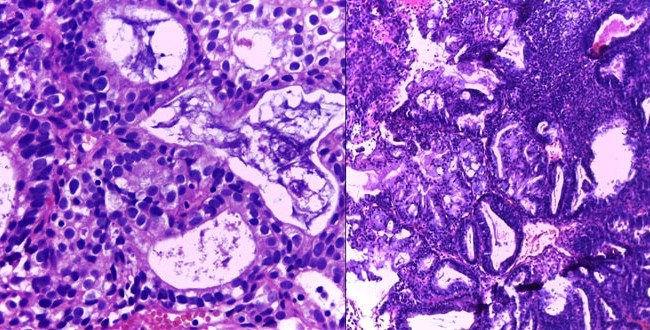

Carcinoma desdiferenciado de endometrio

Autores: Chila Laura; García Kamermann Florencia; Castiglioni Teresa. Centro de patología. El carcinoma desdiferenciado de endometrio es una neoplasia epitelial maligna, poco frecuente, descripta por...